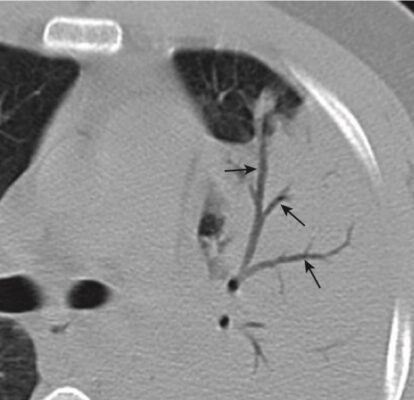

- Bệnh vùng khoang chứa khí có thể có hình ảnh phế quản chứa khí /(khí phế quản đồ)(air bronchogram).

- Khả năng nhìn thấy không khí trong phế quản vì bệnh lý khoang chứa khí xung quanh được gọi là hình ảnh phế quản chứa khí

- Hình ảnh phế quản chứa khí là một dấu hiệu của bệnh lý khoang chứa khí.

- Bình thường không nhìn thấy được phế quản vì thành của chúng rất mỏng, chứa không khí và được bao quanh bởi không khí. Khi một thứ gì đó như chất dịch hoặc mô mềm thay thế không khí bình thường bao quanh phế quản, thì không khí bên trong phế quản trở nên có thể nhìn thấy dưới dạng một loạt cấu trúc hình ống phân nhánh, màu đen – đây là hình ảnh phế quản chứa khí (Hình 3).